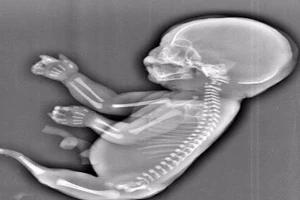

Người mẹ Trung Quốc phá thai vì con là 'người cá'